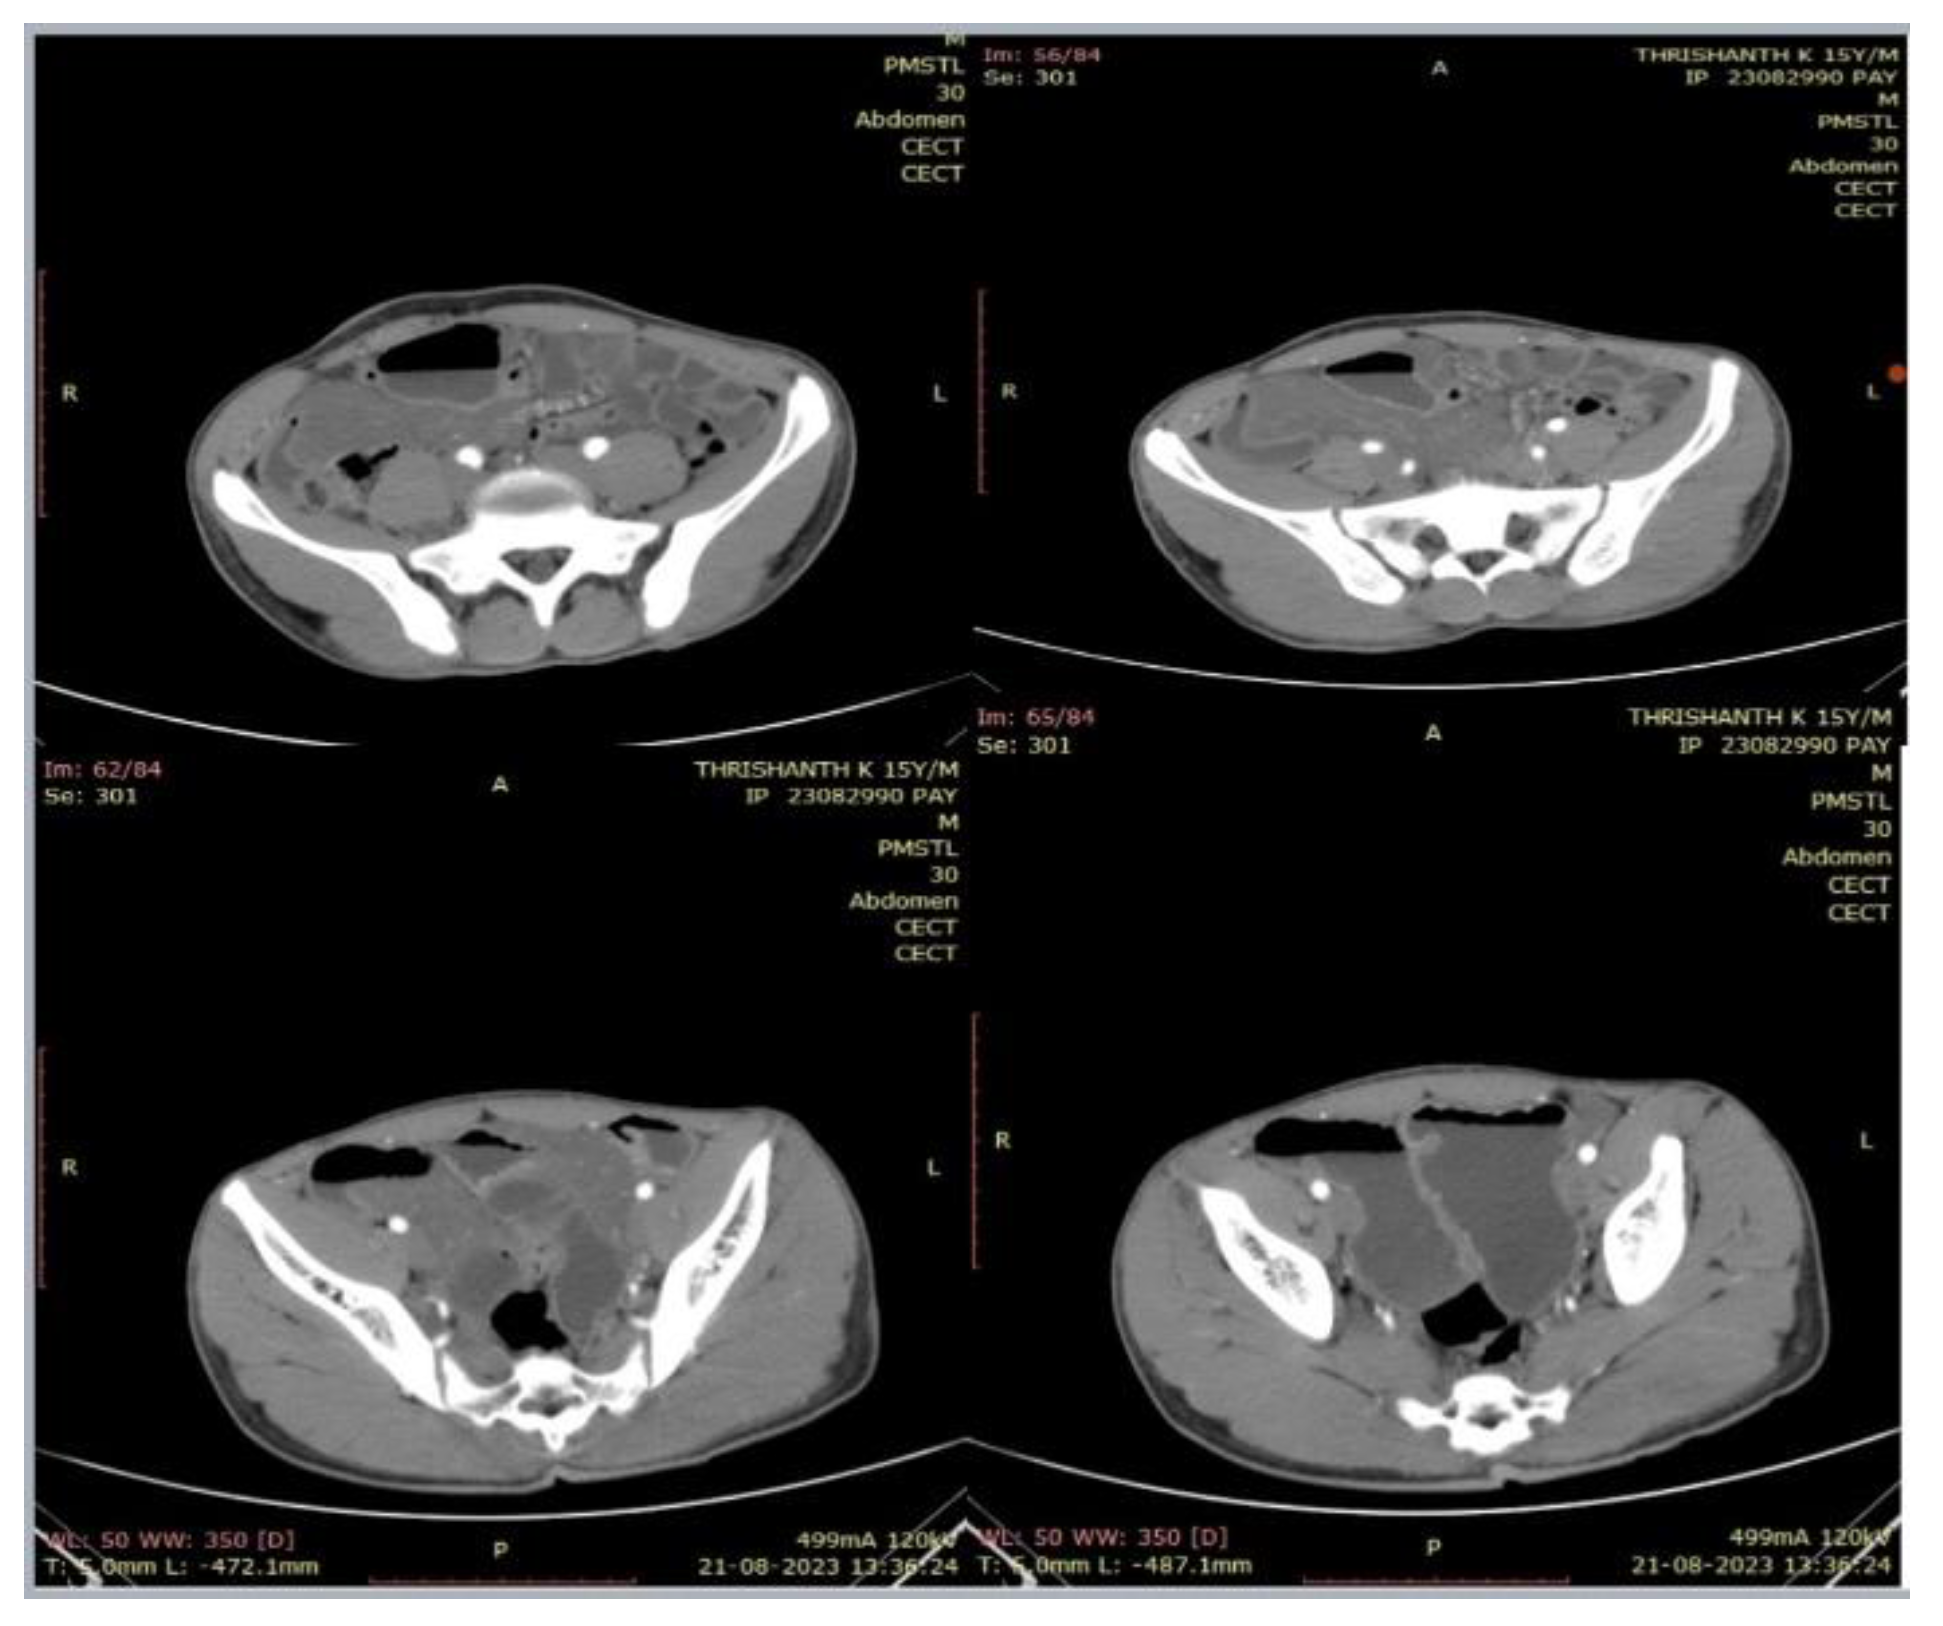

2. Case Presentation